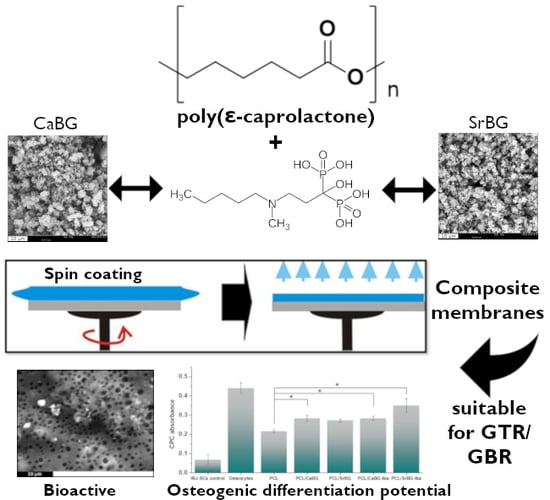

Composite Membranes of Poly(ε-caprolactone) with Bisphosphonate-Loaded Bioactive Glasses for Potential Bone Tissue Engineering Applications

2. Results and Discussion

2.1. Characterization of the Bioglasses

2.2. Characterization of Composite PCL Thin Films

2.2.1. Morphological Characterization

4. Conclusions